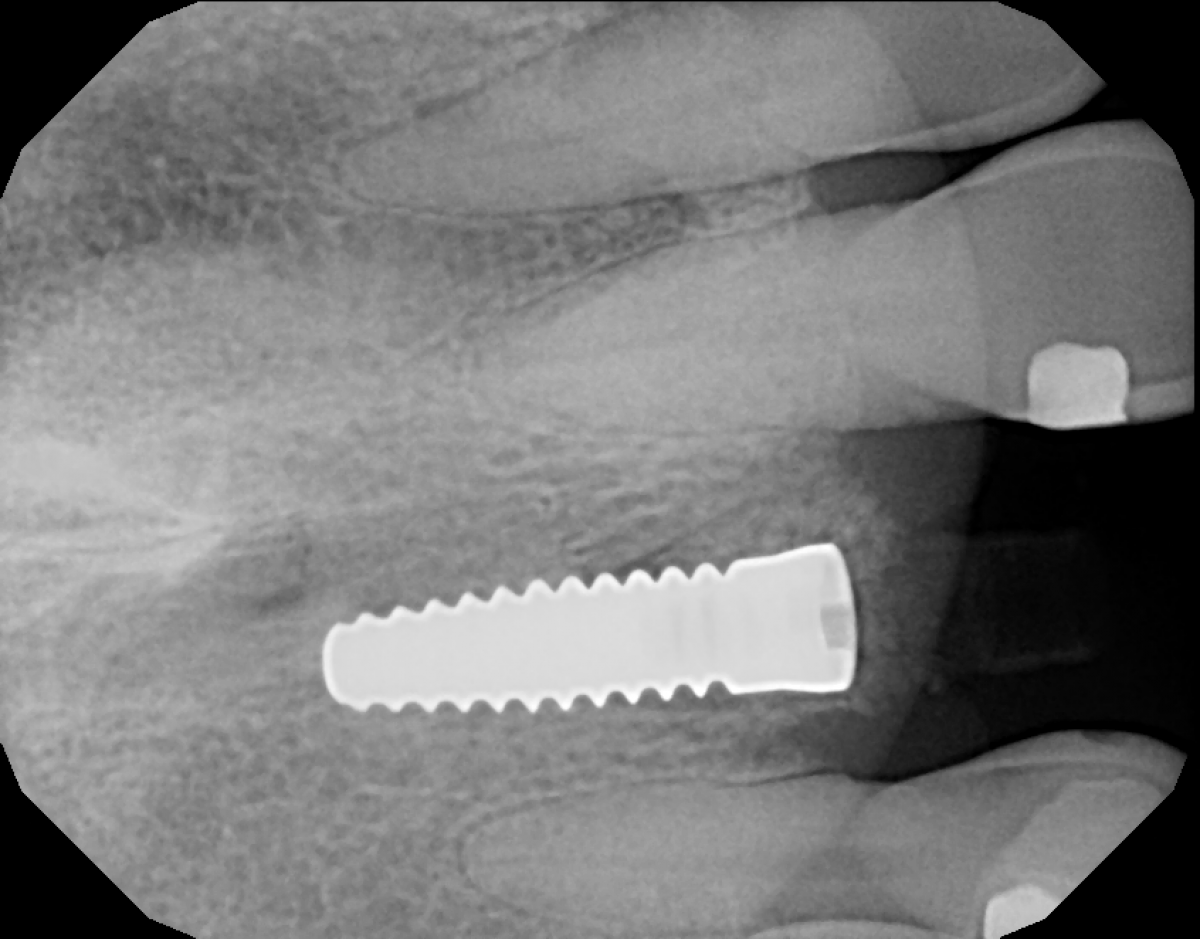

After administering local anesthesia, the tooth was atraumatically extracted, the socket was curetted clean and the presence of a complete buccal wall was confirmed. Osteotomy was done according to manufacturer protocols, with copious irrigation and a 3.5 x 12mm Zeramex XT ceramic implant was placed (Figure 4) at 50 N/cm2 final torque.

The gap was filled with a 50/50 mixture of allograft and xenograft sticky bone prepared with PRF. Implant stability was also measured with Osstell Beacon device to 61 mesio-distally and 61 bucco-lingually. Even though the preferred RFA values for immediate loading are 70 and higher, due to high insertion torque value and other positive contributing factors, immediate provisionalization was chosen.